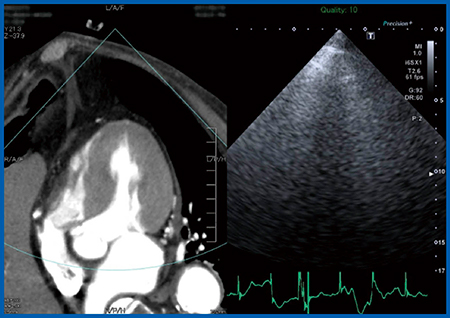

症例は,87歳,男性,高度大動脈弁狭窄症である。既往歴として,腹部大動脈瘤(AAA),狭心症(PCI施行),高血圧,糖尿病があり,AAA術後のため他院通院中に労作時の息切れが出現し,精査目的で当院を受診した。経胸壁心エコー(図1)では左室駆出率(EF)は保たれているが,大動脈弁最大血流速度(peak velocity):4.2m/s,平均圧較差(mean PG):44mmHg,大動脈弁口面積(AVA):0.72cm2,弁口面積係数(iAVA):0.45cm2/m2と,いずれも高度であった。また,CTにてAAAを評価すると,中枢側に大きなAAAが残存しており,蛇行もきわめて強かった。これらの結果から,本症例は,Logistic Euro scoreは25.8%,STS scoreは10.8%と,大動脈弁置換術(AVR)のサージカルリスクがきわめて高かった。

図1 症例:経胸壁心エコー